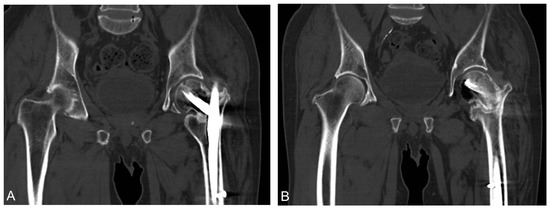

Teriparatide as an Effective Nonsurgical Treatment for a Patient with Basicervical Peritrochanteric Fracture Nonunion—A Case Report

The nonunion rate of surgically treated basicervical peritrochanteric fractures has been reported to be as high as 9%. Due to the high 1-year mortality rate following revision surgery, finding an effective nonsurgical treatment option is of interest. Over the last decade, numerous reports have been published that have suggested teriparatide as an effective treatment for certain types of fracture nonunion. However, the literature focused on teriparatide treatment for proximal femoral fracture nonunion is scanty. A 70-year-old man suffering from a left hip basicervical peritrochanteric fracture received cephalomedullary nail fixation. Nine months after the surgery, the patient still complained of left hip pain referring to the medial thigh with an antalgic limping gait. No sign of healing was noted for more than a consecutive 3 months of follow-up. Fracture nonunion was diagnosed and further confirmed by the computed tomography (CT). The patient preferred nonsurgical treatment after thorough discussion. He then received 4 months of subcutaneous teriparatide injections, 20 mcg daily. After less than 4 months of teriparatide treatment, a follow-up CT confirmed fracture union and the patient’s pain subsided. The patient also tolerated independent ambulation afterward. Teriparatide has been reported to be an effective treatment for certain types of fracture nonunion. Our case goes a step further to expand its possible application for basicervical peritrochanteric fracture nonunion. However, further larger scale studies are needed to confirm its efficacy. Full article

Show Figures

Figure 1